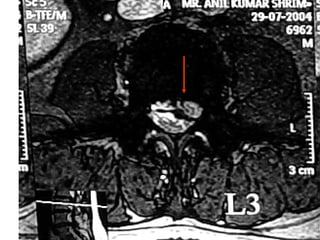

Case summary –  Delayed reporting Backache sciatica Lt 3 months Had localized pain around knee joint